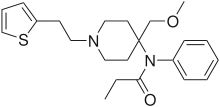

Anilidopiperidines

- 3-Allylfentanyl

- 3-Methylfentanyl

- 3-Methylthiofentanyl

- 4-Phenylfentanyl

- Alfentanil

- α-Methylacetylfentanyl

- α-Methylfentanyl

- α-Methylthiofentanyl

- Benzylfentanyl

- β-hydroxyfentanyl

- β-hydroxythiofentanyl

- β-Methylfentanyl

- Brifentanil

- Butyrfentanyl

- Carfentanil

- Fentanyl

- Lofentanil

- N-Methylcarfentanil

- Mirfentanil

- Ocfentanil

- Ohmefentanyl

- Parafluorofentanyl

- Phenaridine

- R-30490

- Remifentanil

- Sufentanil

- Thenylfentanyl

- Thiofentanyl

- Trefentanil

Structures